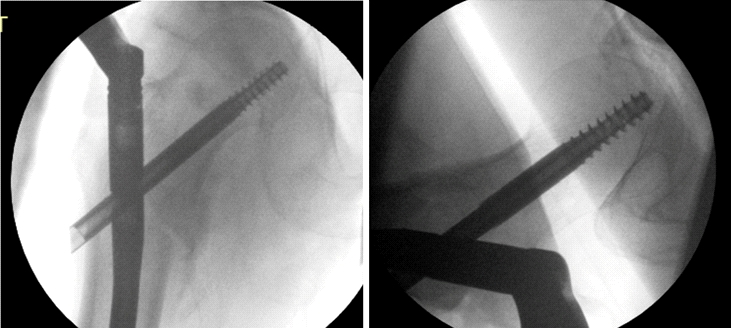

再次外伤后,拉力螺钉上内侧移位

螺钉取出后的X线片显示骨折不愈合。